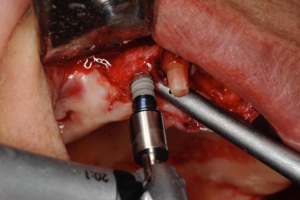

2.埋入したインプラントは縫合して骨に付く(オッセオインテグレーションといいます)のを待ちます。期間は3〜6ヶ月です。

3.骨が付いたら再度歯肉を切開して(2次オペれーションといいます)アバットメント(土台)をインプラントの上に付けて型をとります

2次オペ切開